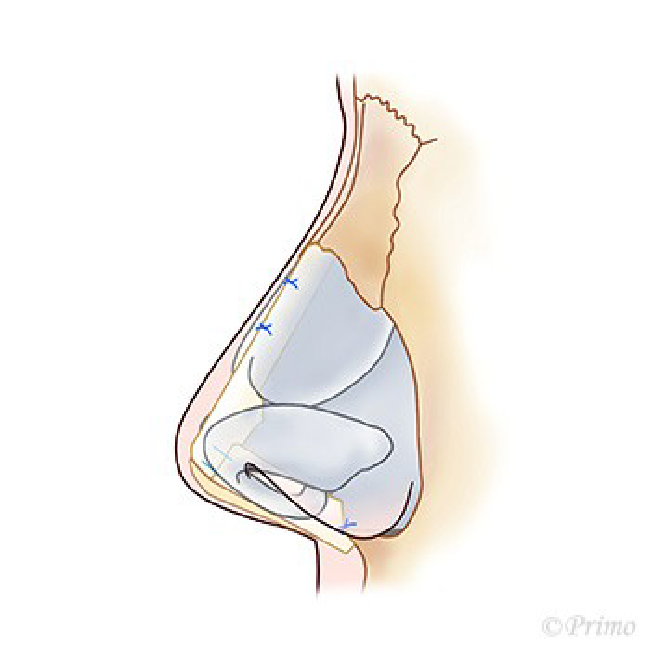

求める変化の大きさ、もともとの鼻の状態に応じ、採取部位を耳介軟骨、肋軟骨、あるいは鼻中隔軟骨から選択し、必要量のみ採取いたします。(上の図は耳介軟骨を採取して鼻中隔延長をするイメージ)

耳介軟骨からとる場合は、耳の後ろのしわに沿って約2cm程の傷から採取します。傷はほとんどわからなくなり、耳の変形も、機能障害もきたしません。

肋軟骨からとる場合は、バストのアンダーの位置に約3cm程の傷から採取します。傷は最小限になるよう形成外科縫合を行います。移植材料となる軟骨が大きくとれるので、大きな変化を求める場合や、術後の修正例の場合に適しております。採取部の変形などはありません。

鼻中隔軟骨から採取する場合は、軟骨が小さいため、それほど大きな変化を望まない場合などになります。別の所に採取部の傷を残さない良い方法です。(下の図は鼻中隔)

アプローチは経鼻柱切開(オープンアプローチ)から、術野を広く展開し、確実に操作を行います。鼻中隔軟骨に移植軟骨を組み合わせ延長し鼻の向き、高さを変えていきます。ご希望に応じ鼻の脂肪を部分的に除去し細っそりとさせたり、インプラントによる隆鼻術を併用し、より印象的な鼻に変化させます。鼻柱の傷あとはあまり目立ちません。

青い部分が移植した軟骨です。この軟骨の固定により、鼻の高さ、細さ、向きが大きく調節できます。